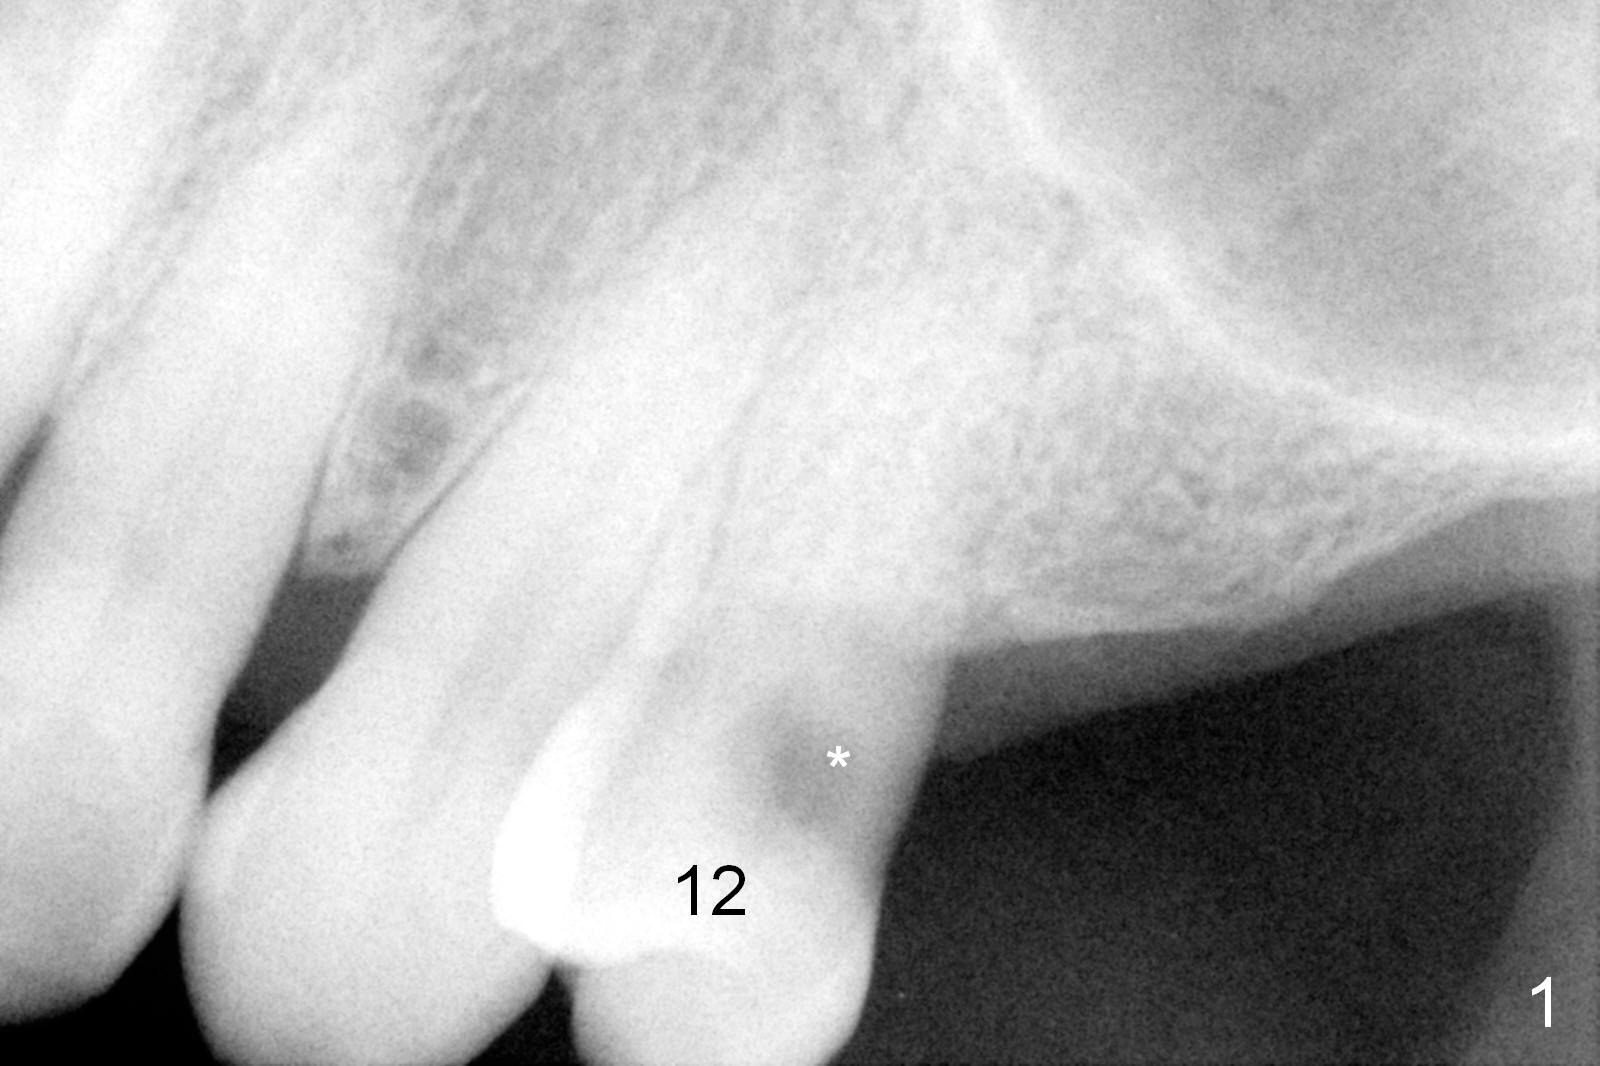

A 64-year-old man (MM) had caries at the tooth #12 (Fig.1), requiring root canal therapy (RCT, Fig.2). One year later, the periapical radiolucency reduces (Fig.3 <, as compared to that in Fig.2). The tooth remains asymptomatic 7 years posts RCT (Fig.4). A year later, the tooth has pain and buccal gingival swelling (probing tenderness); periradicular radiolucency is evident (Fig.5 arrowheads). It appears that the root fractures. Between the 7th and 8th years post RCT, the patient masticated mainly on the left side, while implants were placed at #30 and 31. The patient plans to have 4 implants in the upper left sextant (Fig.6). While implants are being placed at the site of #12 (Clindamycin) and 13, sinus lift seems mandatory at the sites of #13 and (initial depth will be 5-6 mm). By the time implants to be placed at #14 and #15, the bone height may increase.